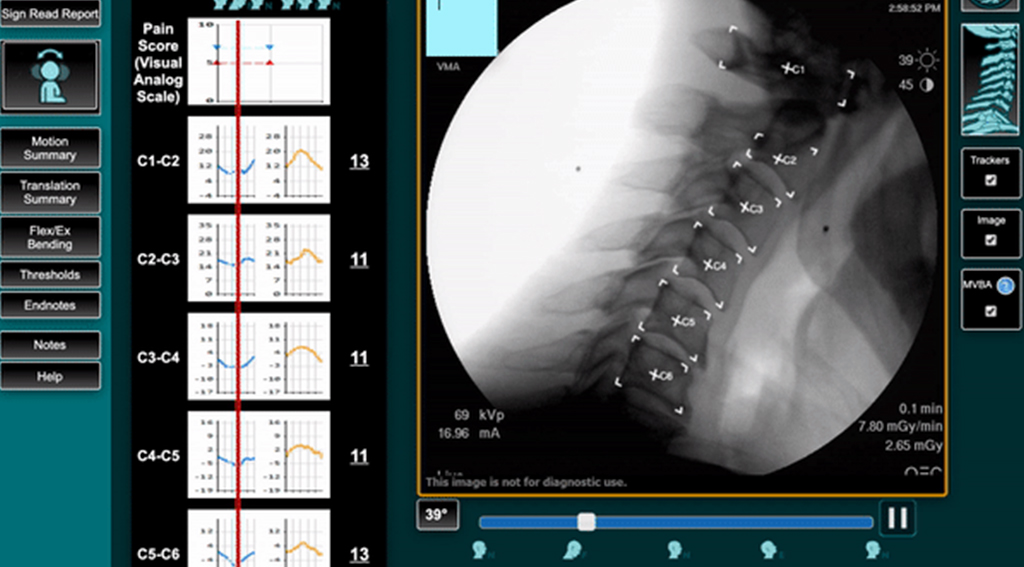

At TruePath Imaging, you receive motion-based spine imaging that shows what traditional tests miss. VMA® (Vertebral Motion Analysis) evaluates how your spine moves under stress, revealing instability that can lead to pain or functional loss.

Spine imaging has relied heavily on static views such as X-ray and MRI. These studies show structure well, yet they limit how motion, instability, and subtle ligament injury appear. TruePath Imaging adds a different layer with Vertebral Motion Analysis, a dynamic study designed to measure spinal motion with precision. VMA reveals abnormal movement patterns that static images overlook, providing objective data early in evaluation and documentation.

See spinal motion in real time and identify instability that static imaging misses. Learn how VMA strengthens diagnosis and treatment planning.

VMA shows what static imaging misses.

It captures the spine in motion, revealing instability that X-rays and MRIs often overlook.

VMA delivers objective, measurable findings.

Its technology provides precise motion data in millimeters and degrees, not subjective interpretations.